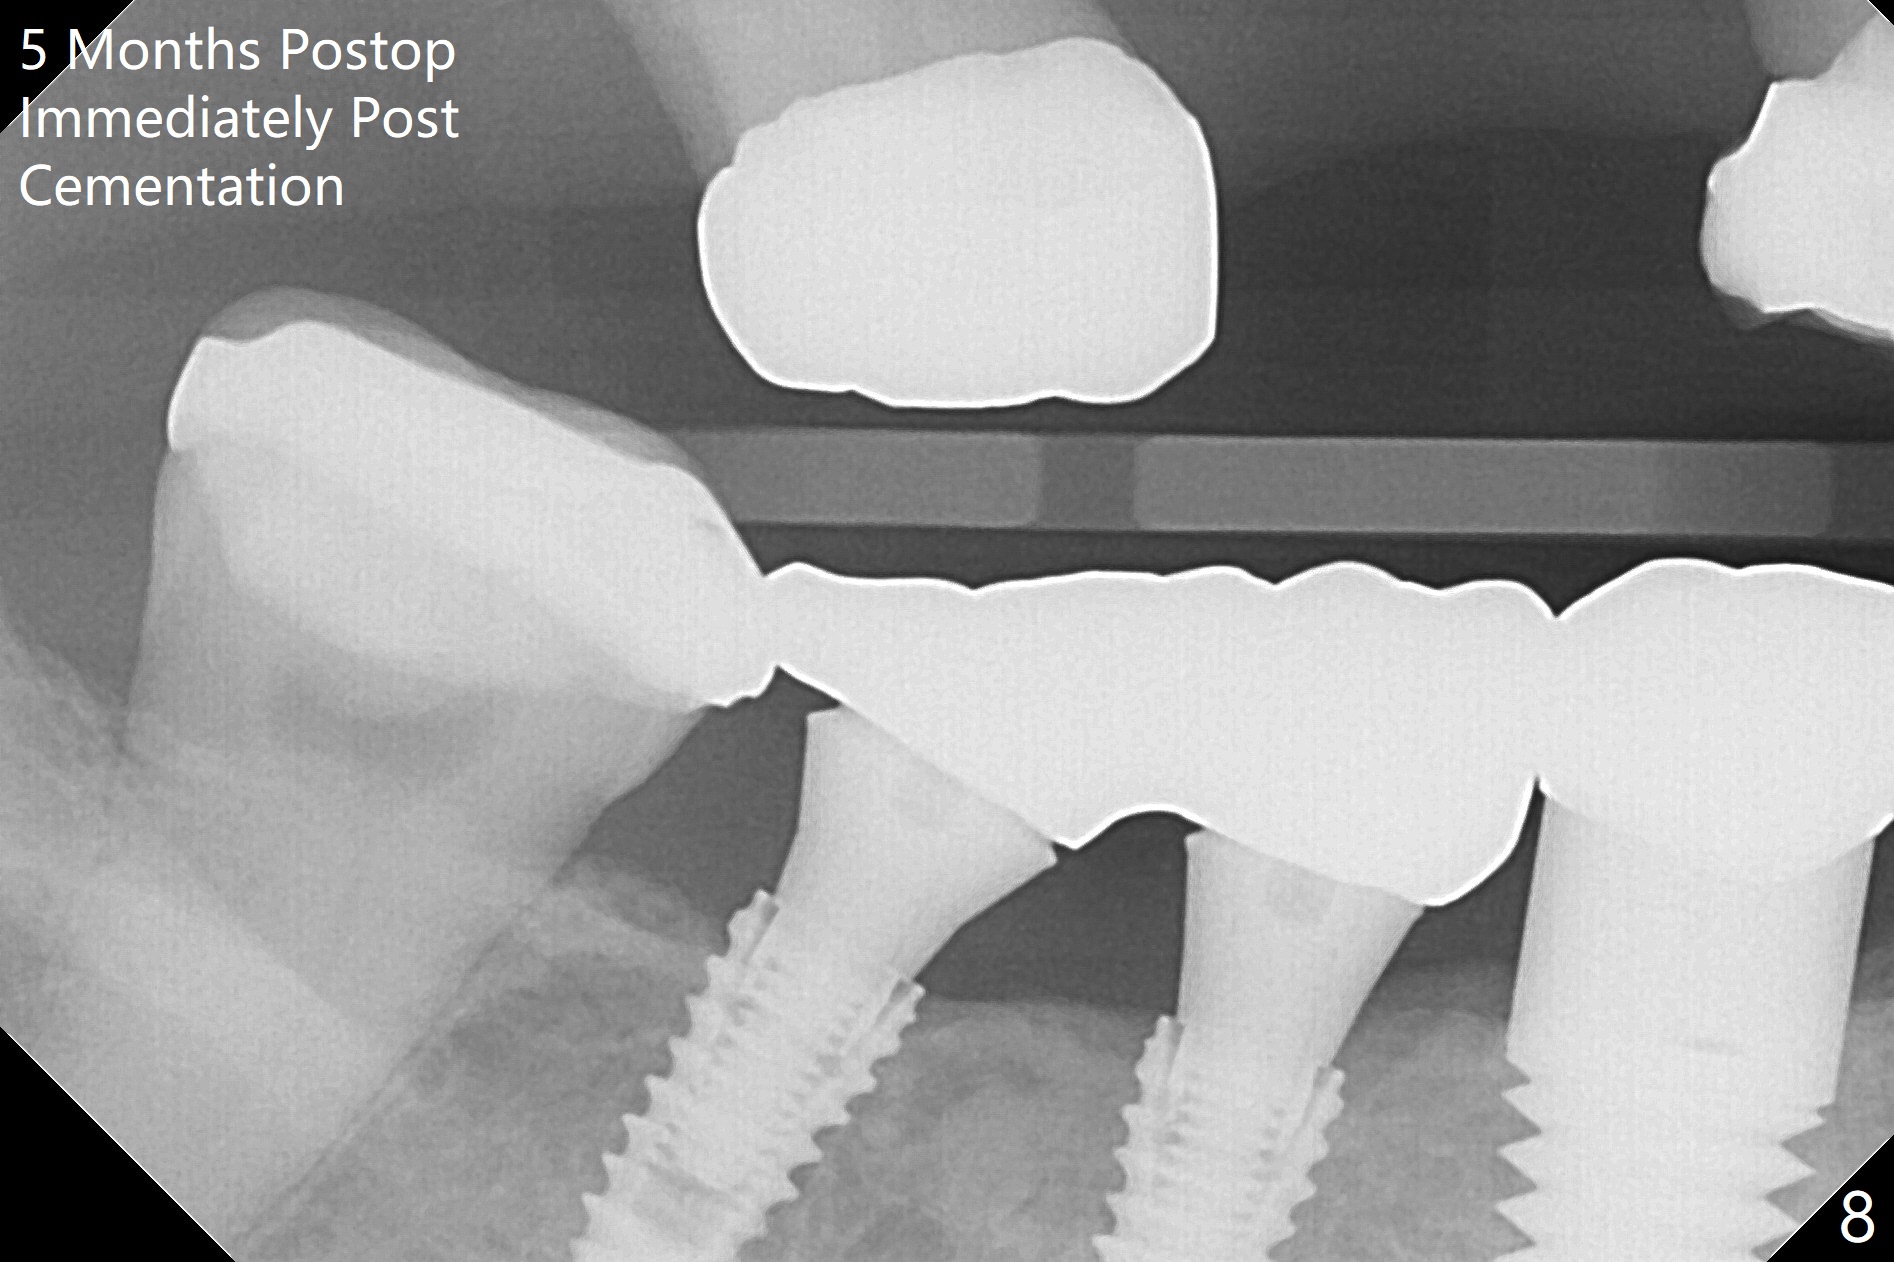

The patient with history of bruise after minor trauma returns next day. There is oozing from the site of #31. Hemostasis is achieved following periodontal dressing application and 2x2 gauze pressure. There is mild crestal bone resorption 4 months postop (Fig.7). Because of limited vertical space, the provisionals have dislodged by the time of cementation. It is difficult to seat the splinted crowns of #30 and 31. Bitewing is taken after cementation: the crowns have open margin (Fig.8). When a crown has high occlusion, X-ray should be taken prior to cementation.